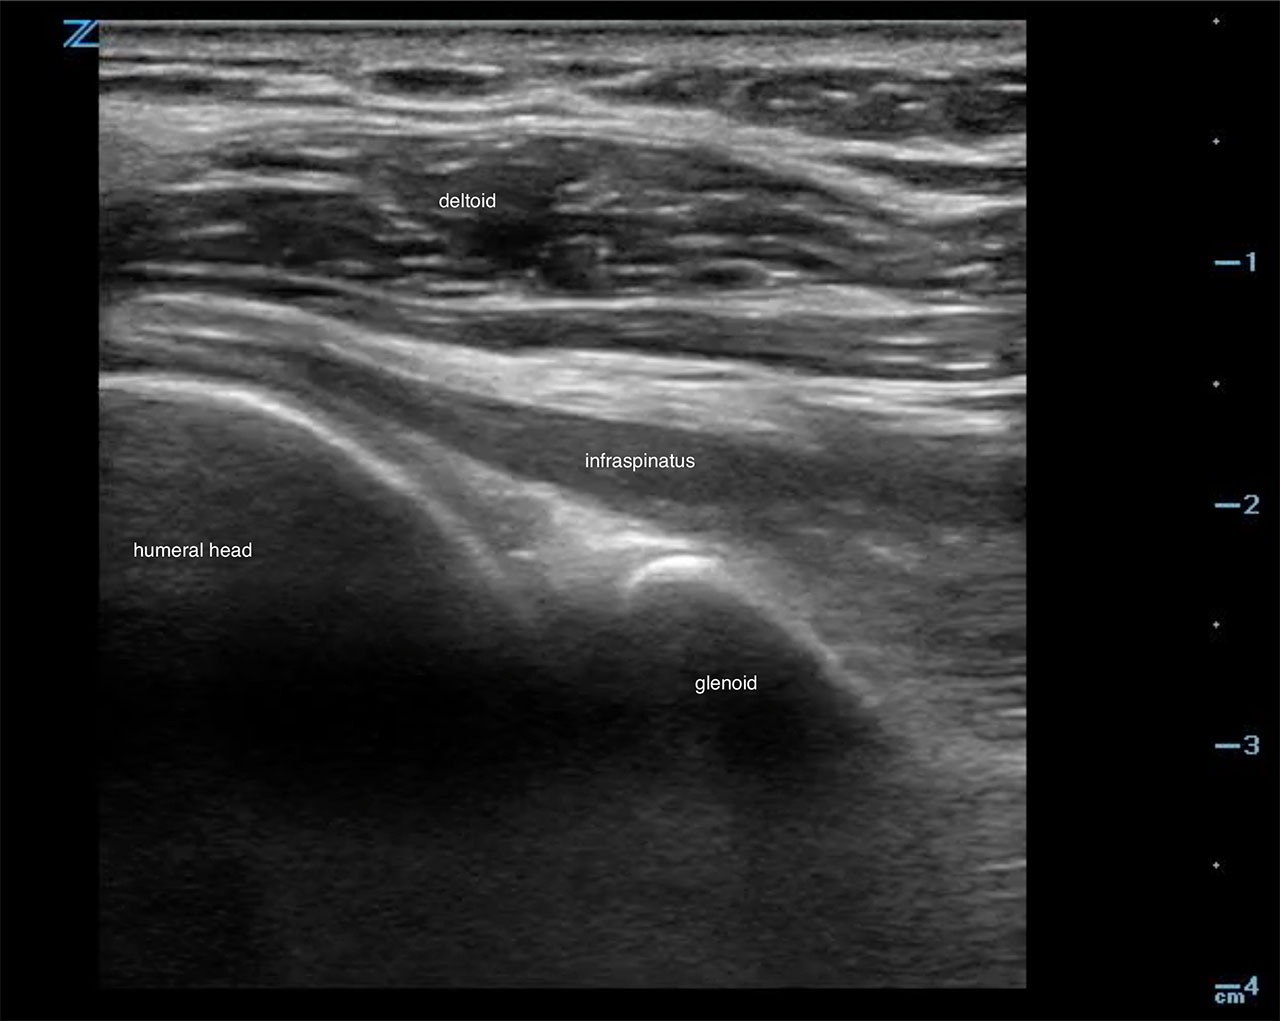

Shoulder

- The humeral head appears hyperechoic laterally.6

- It articulates with the glenoid fossa and contains infraspinatus tendon superficially.

- Posterior approach

- Linear or curvilinear transducer (choice based on body habitus)

- Transducer transverse below the scapular spine. Marker to the patient’s left (Fig. 8)

- Figure 8. Transducer placement for shoulder joint evaluation

- Scan laterally toward the humerus to obtain a view of the humeral head, glenoid fossa and superficially the infraspinatous tendon.6 (Fig. 9, Video 2)

- Figure 9. Ultrasound demonstrating normal shoulder

- Video 2. Ultrasound demonstrating normal shoulder motion with internal and external rotation

- An effusion is an anechoic collection just above the head of the humerus